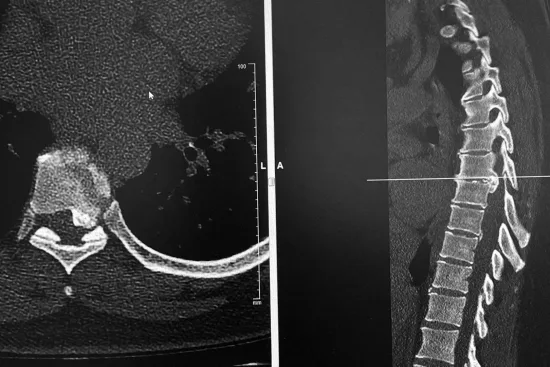

Los discos dorsales son tejidos semejantes a un cojín esponjoso que se encuentran entre las vértebras de la columna. Las hernias aparecen cuando uno de los discos sobresale de entre las vértebras, presionando los nervios y la médula, lo que produce dolor y otros síntomas como la sensación de hormigueo, dependiendo del lugar en el que se originen.

Es común que con la edad, el material gelatinoso que amortigua los discos se debilite y desaparezca, posibilitando movimientos que los desvíe de su posición original, produciendo de esta manera una hernia. Cuando el disco llega a presionar la médula o algún otro nervio importante, es posible que el paciente presente sensación de adormecimiento en las extremidades y, en casos más graves, debilidad en las extremidades o dificultad para el movimiento.

Existen diferentes maneras de detectar una hernia discal, pero en todo caso, es el especialista médico el que debe valorar al paciente y especificar el método de diagnóstico que mejor se adapte a sus necesidades y a la naturaleza de su lesión. El tratamiento dependerá de la gravedad de la hernia. Por regla general, el tratamiento es inicialmente conservador con el uso de medicamentos, reposo, rehabilitación e infiltraciones en su caso.